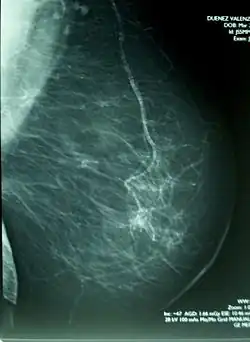

Głównym celem prowadzenia diagnostyki mammograficznej jest wykrycie u osób bez widocznych objawów chorobowych nowotworów piersi we wczesnym stadium. Jest to możliwe dzięki różnicom w pochłanianiu promieni rentgenowskich przez poszczególne tkanki organizmu. W miejscach rozwoju raka przewodowego tworzą się mikrozwapnienia, które na kliszy radiograficznej uwidaczniają się w postaci układów białych plamek. W grupie osób z wynikiem pozytywnym stosuje się inne diagnostyczne metody obrazowania piersi (ang. diagnostic breast imaging), które mają doprowadzić do postawienia ostatecznego rozpoznania. W wypadkach niepewnych wykonuje się biopsję zmiany.

W przypadku zaistnienia nieprawidłowości można stwierdzić[64][65]:

- patologiczne przejaśnienia lub cienie różnego kształtu i wielkości (okrągłe, z postrzępionymi brzegami, z gwiaździstymi wypustkami)

- mikrozwapnienia, w formie układów jasnych punktów („spikularne” lub liniowe z rozgałęzieniami)